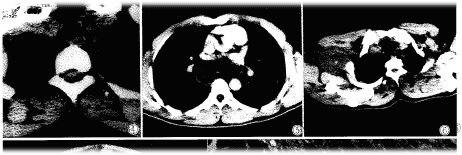

纵隔内神经鞘瘤,除1例位于椎体前方外,其余均位于脊柱两旁,边缘光滑,宽基底与脊柱相连,密度一般均匀(图4),2例呈低密度(类似水样密度)CT值13-19Hu,其余8例密度均匀低于或等于肌肉密度,增强扫描1例无强化(图5),4例不均匀强化。胸椎及肋骨骨质未见明确破坏和吸收,肿瘤未侵入椎管内。

臂丛神经鞘瘤呈圆形,类圆形软组织块影,位于臂丛神经走行区或与之关系密切的部位,CT平扫肿块低于或略低于肌肉密度(图6),边缘光滑。增强扫描高于肌肉低于血管。

图1腰5椎管内神经鞘瘤椎间盘突出术后二年,腰5右侧神经根增粗,呈圆形软组织密度影。图2颈7椎管内神经鞘瘤,脊髓向前受压变扁,蛛网膜腔增宽扩大。图3颈动脉鞘区偏后神经鞘瘤,增强扫描强化不均匀,血管受压向前移位。图4纵隔神经鞘瘤宽基底与脊柱相连,边缘光滑,密度均匀。图5纵隔神经鞘瘤增强扫描,边缘轻度强化,中心不强化。图6臂丛神经鞘瘤,边缘光滑,密度均匀。图7腹腔恶性神经鞘瘤,肿瘤不规则,密度不均,见大片液化坏死区。图8神经鞘瘤病理见瘤细胞呈栅栏状改变(×40)